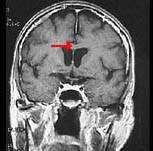

如图箭头所示为大脑哪个部位 ( )A、穹窿B、中脑导水管C、胼胝体D、透明隔E、前连合一、单项选择题

问题 如图箭头所示为大脑哪个部位 ( )

选项 A、穹窿 B、中脑导水管 C、胼胝体 D、透明隔 E、前连合 一、单项选择题

答案 C